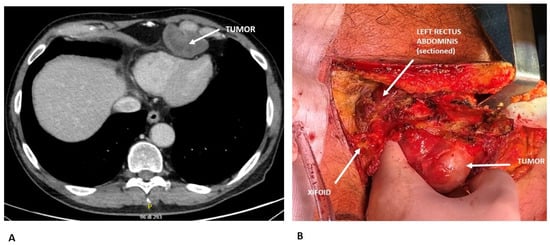

Radiological diagnosis of chest wall tumors can be challenging due to their considerable histological diversity. Moreover, imaging alone often cannot reliably differentiate between benign and malignant lesions. Therefore, an integrated approach using multiple imaging modalities is recommended. The most commonly employed techniques include chest X-rays, computed tomography (CT), magnetic resonance imaging (MRI), and positron emission tomography (PET). Chest X-rays are typically the first imaging modality used. They help identify the location and size of the lesion and may reveal features such as calcification, bone erosion, or destruction. Certain bone tumors of the chest wall display characteristic radiographic patterns that can facilitate diagnosis; however, early-stage tumors may be overlooked. In some cases, conventional radiography can provide sufficient information for diagnosis, potentially obviating the need for a tissue biopsy [18]. CT imaging offers higher sensitivity and specificity than chest X-rays, providing superior resolution. When performed with contrast, CT enables detailed assessment of the tumor’s extent and its relationship with surrounding structures, including the lungs, pleura, mediastinum, and regional lymph nodes. Additionally, CT can offer insights into tumor density, vascularity, and internal composition [18] [Figure 1]. MRI is particularly valuable for precise tissue characterization and superior spatial resolution. It is especially useful in distinguishing chest wall tumors from infectious or inflammatory conditions, enhancing diagnostic accuracy [19,20,21]. PET is a non-invasive modality that allows for the evaluation of disease presence and extent. It is particularly useful in staging and monitoring treatment response, especially for sarcomas. Studies have reported a sensitivity of 88% and a specificity of 92% for detecting high-grade local sarcoma recurrences, underscoring its important role in clinical management [22] [Table 2].

Figure 1. (A) Preoperative CT scan showing a chondrosarcoma arising from the 6th costo-chondral junction and compressing the cardiac surface. Radiological features suggesting chondrosarcoma: lobulated, expansive bone lesion with well-defined margins; internal low attenuation due to high water content of the cartilaginous matrix; soft tissue extension beyond the bone. (B) Intraoperative view demonstrating surgical resection of the chondrosarcoma.